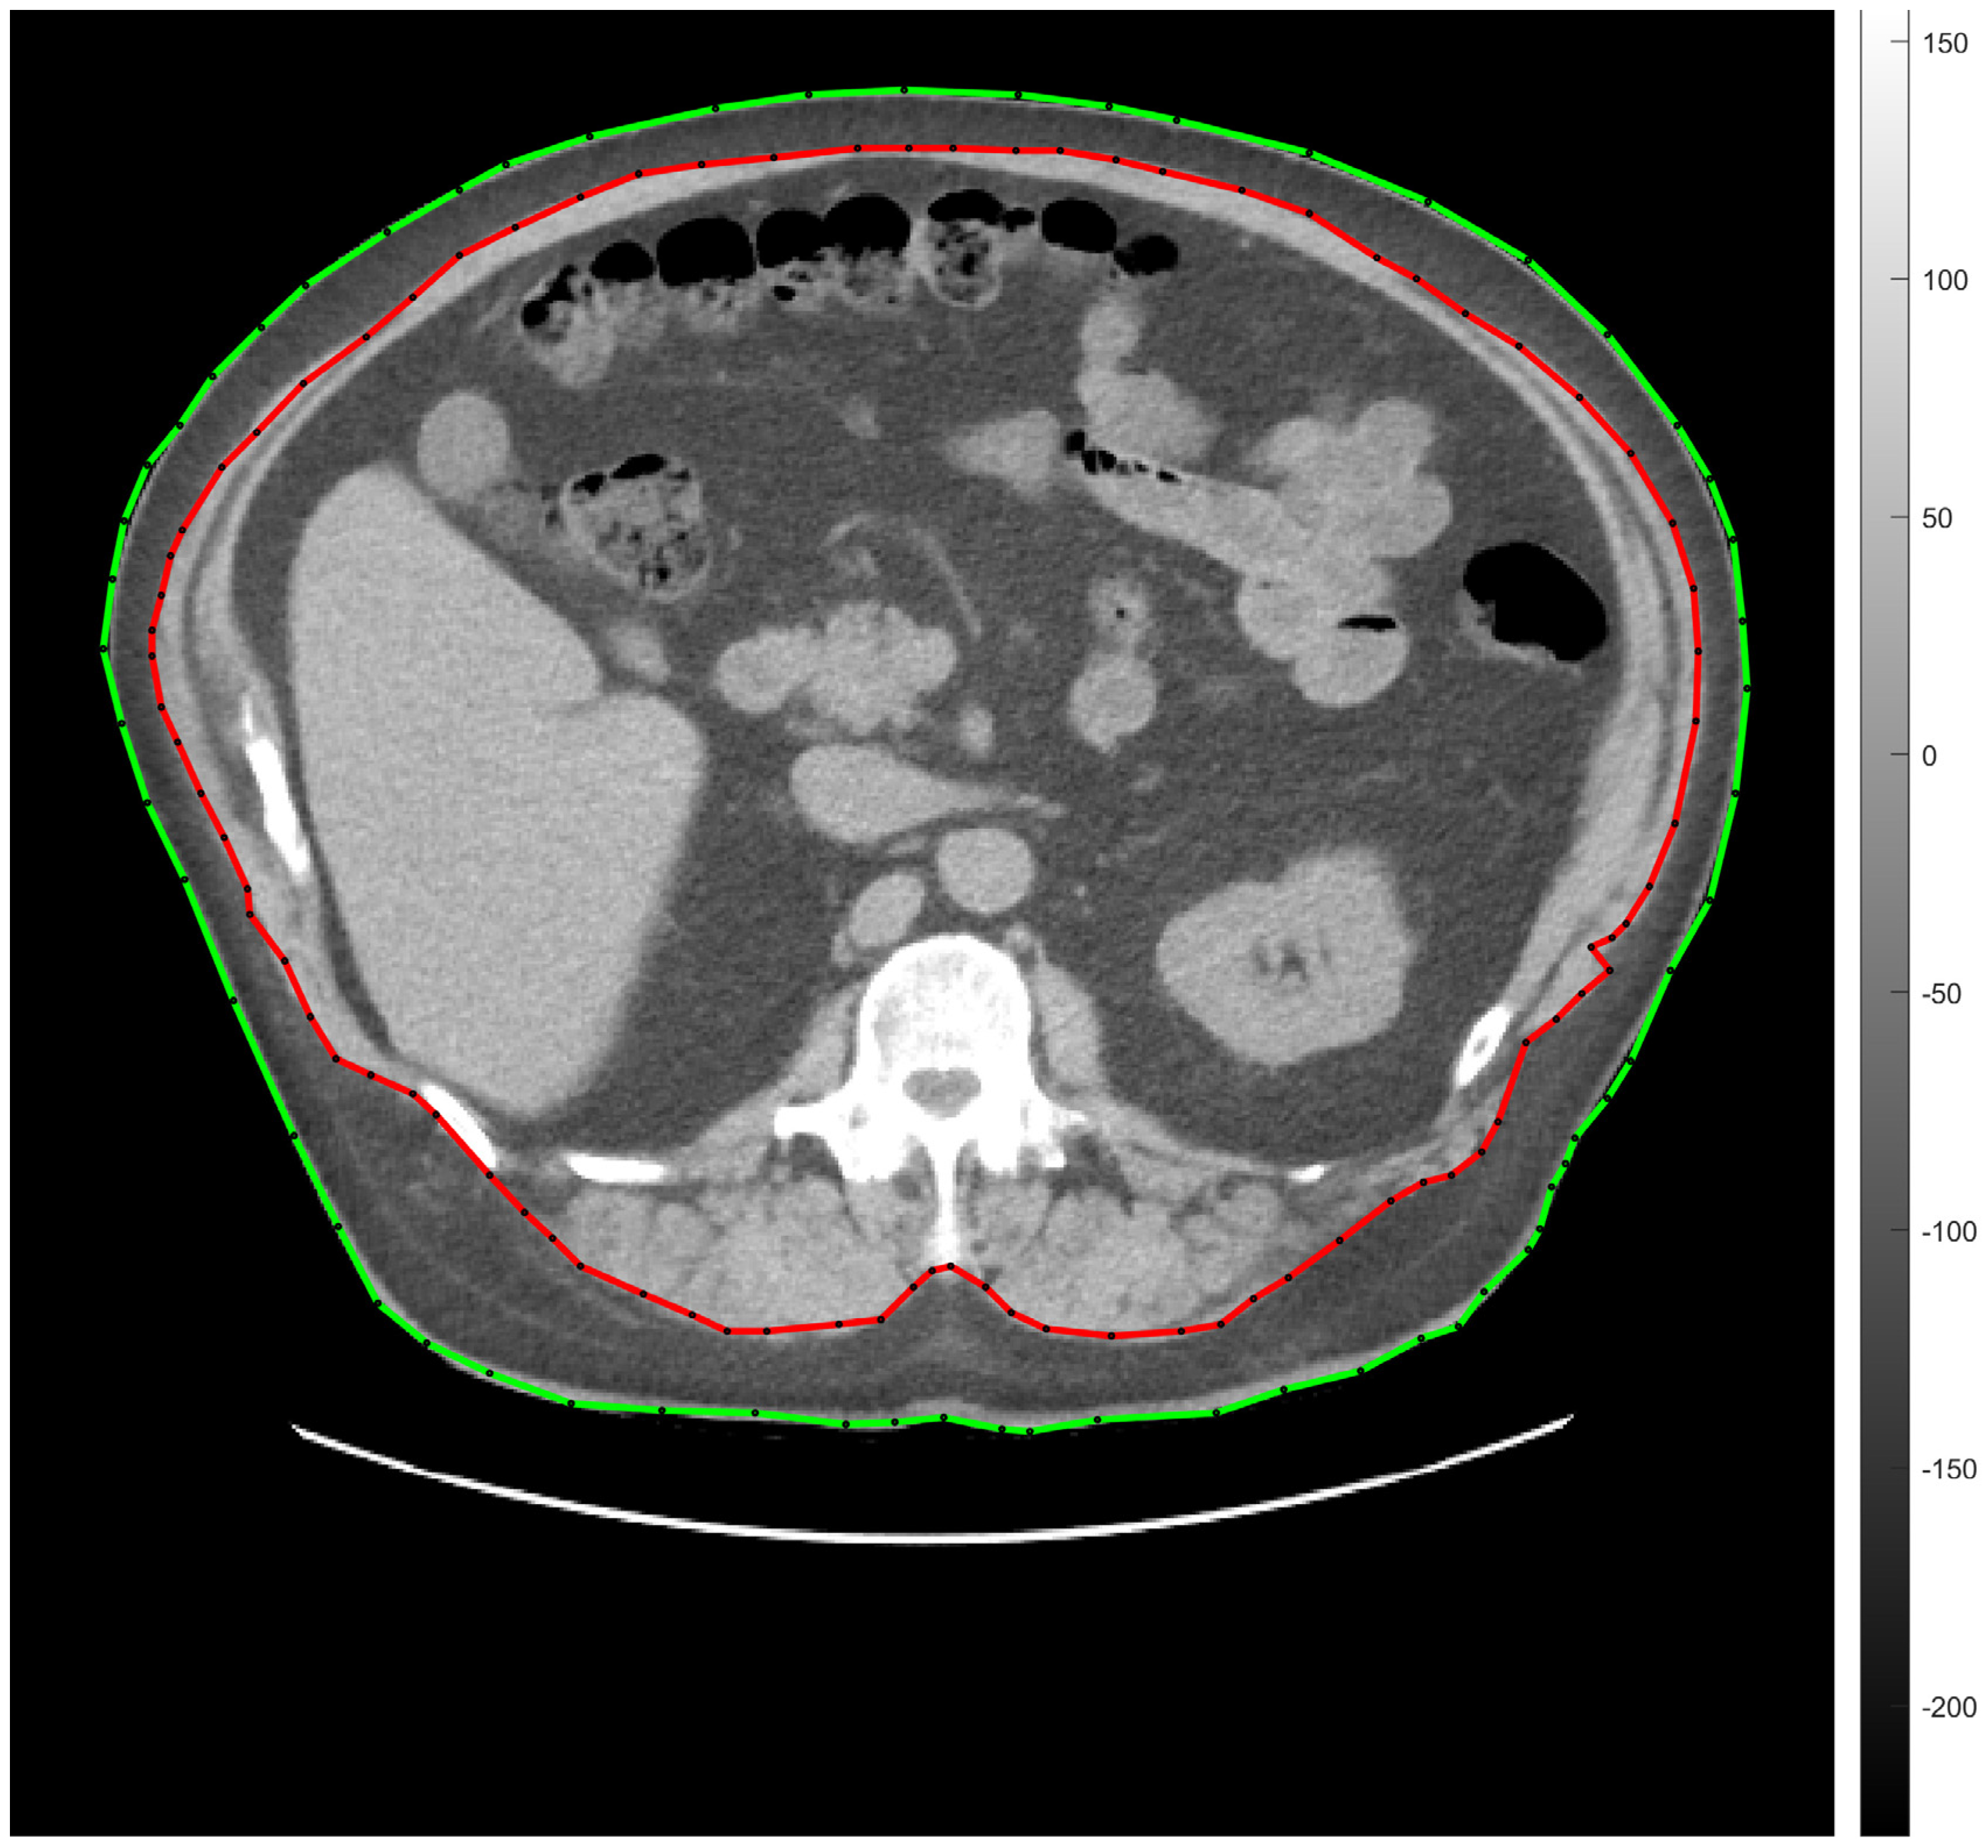

2.7. Abdominal Fat Tissue Segmentation

- Egeresi, L.; Székely, A.; Kallos-Balogh, P.; Trón, L.; Garai, I.; Balkay, L. Effect of Single-Slice CT Segmentation Methods on Fat Volume and Body Shape Estimation. Acta Polytech. Hung. 2023, 20, 267668968. [Google Scholar] [CrossRef]